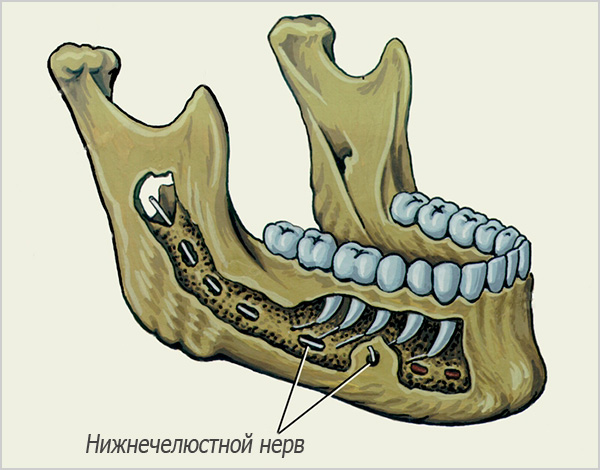

Danos na parede do canal mandibular e nervos da mandíbula

Essa complicação durante implantes dentários nem sempre tem consequências negativas a longo prazo, porque, apesar do nome assustador, na verdade se manifesta geralmente apenas como dormência na mandíbula inferior (na maioria das vezes os lábios ficam dormentes). Mesmo sem tratamento, esses sintomas podem desaparecer por conta própria dentro de 2-3 semanas, com um máximo de 2-3 meses.

Além disso, deve-se ter em mente que a sensação de dormência no lado correspondente da face também pode ser uma conseqüência da compressão do nervo no canal mandibular. Às vezes, isso ocorre devido ao sangramento nos espaços da medula óssea - o sangue pode fluir não apenas em direção à cavidade oral, mas também se mover gradualmente pelos espaços do osso, porque o tecido intraósseo da mandíbula não é "sólido", mas celular. A entrada de até uma quantidade relativamente pequena de sangue na região da passagem do nervo mandibular no canal cria uma compressão temporária. Gradualmente, as massas sanguíneas se dissolvem, mas leva algum tempo quando o nervo se recupera de um efeito tão compressivo (geralmente não mais que 5-7 dias).